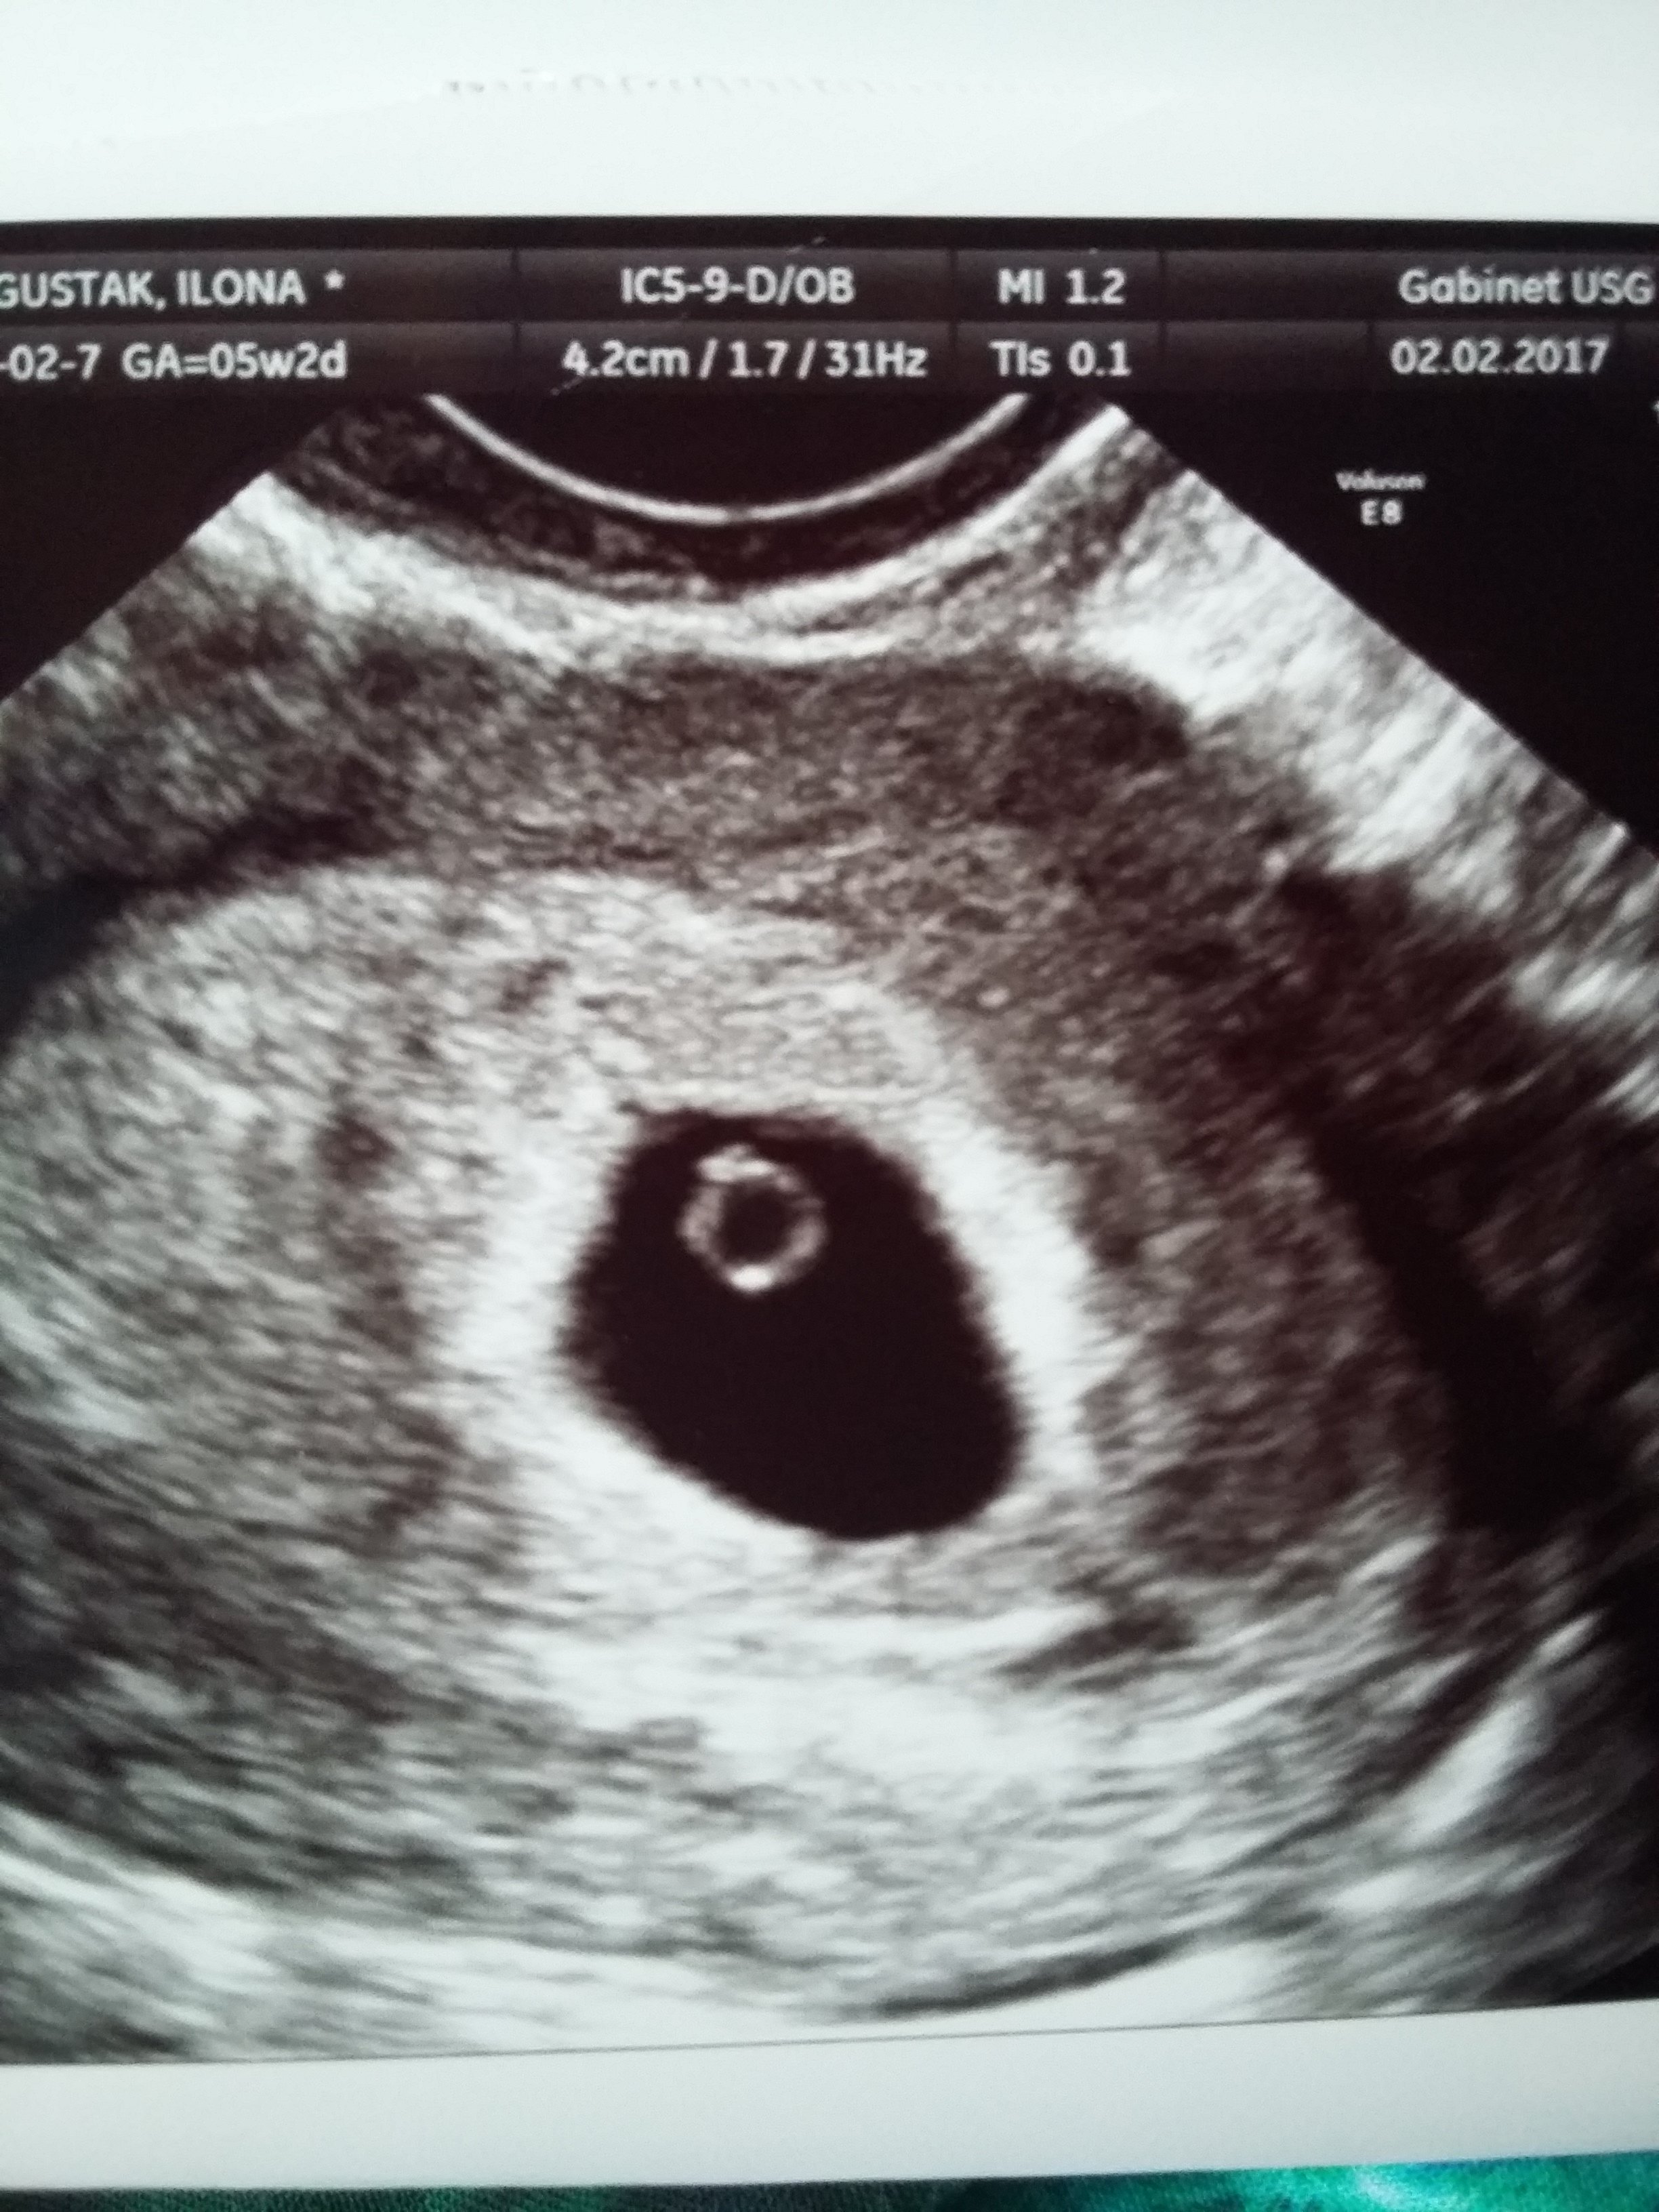

Super![emoji7]Fajnie że poszłaś, będziesz spokojniejsza [emoji178]Ja już po wizycieokazało się ze ciąża dużo młodsza, 5 tc zarodek 3 mm. Serduszka jeszcze nie słuchałam, za 2 tygodnie będziemy słuchać. Ciąża pojedyncza

Kurcze te pomiary są fajne [emoji38]Ja już po wizycieokazało się ze ciąża dużo młodsza, 5 tc zarodek 3 mm. Serduszka jeszcze nie słuchałam, za 2 tygodnie będziemy słuchać. Ciąża pojedyncza

Przedstawiam Wam moja kropeczkę kochana, która ma 1.39 cm ♡ według OM 5t4d a wg usg 4t4d

To pewnie wymiar pęcherzyka a nie zarodka [emoji6]Buczulinda niech zdrowo rośnie fasolka :-)

Bo to jest rozmiar pęcherzyka a nie zarodka. Zarodka nie widać jeszcze. I nie wiem czy nie powinnam się tym martwić.. No ale lekarz powiedział że na tą chwilę jest wszystko dobrzeBuczulinda niech zdrowo rośnie fasolka :-)